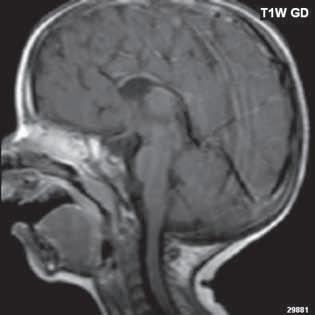

Při agenezi corpus callosum CT i MR zobrazí paralelní průběh postranních mozkových komor (oproti fyziologickému

konvergentnímu průběhu) a jejich oddálení, časté rozšíření okcipitálních rohů – colpocefalie, někdy středočárový lipom, cystu. Koronální řezy ukážou rozšíření frontálních rohů postranních komor, III. komora je situována vysoko mezi postranní komory, tvoří jakoby trojzubec, který někteří autoři přirovnávají k přilbě Vikinga. Není patrné septum pellucidum. Častá je přítomnost středočárového lipomu nebo cysty.

Na vnitřní straně postranních komor pozorujeme v T2W obrazu poněkud tmavší strukturu než okolní myelinizovaná vlákna (naopak v T1W obrazu zvýšený signál), Probstovy provazce, axony, které za fyziologických okolností přecházejí přes corpus callosum do kontralaterální hemisféry.

Sagitální řezy nám přinášejí nejvíce informací o corpus callosum. Pozorujeme radiální průběh mozkových sulků ke stropu III. komory na vnitřní straně mozkových hemisfér a naopak nezobrazíme gyrus cinguli. Při parciální agenezi je postiženo především splenium.

Obr. I.1.2a Paralelní postavení postranních komor, kolpocefalie, ageneze corpus callosum

Obr. I.1.2b Ageneze corpus callosum

Obr. I.1.2c Ageneze corpus callosum, frontální rohy postranních komor mají tvar rohů na Vikingské helmě, kraniálně uložená III komora

Obr. I.1.2d Ageneze corpus callosum, intrauterinní vyšetření (gestační stáří 23 + 5)

Obr. I.1.2e Ageneze corpus callosum, frontální rohy postranních komor mají tvar rohů na Vikingské helmě, kraniálně uložená

III komora, Probstovy provazce (šipka)